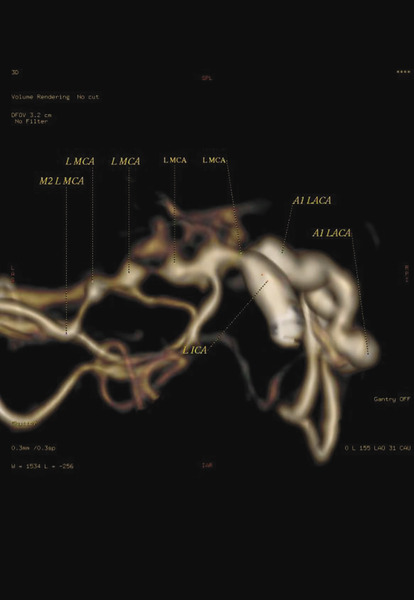

Rycina 3. Tomografia komputerowa naczyń mózgowych (angio-TK). Widoczne obustronne krytyczne zwężenie lub niedrożność w początkowych odcinkach przedniej i środkowej tętnicy mózgu, z lepiej rozwiniętym krążeniem obocznym prawej półkuli mózgu

Wykonano TK naczyń domózgowych i mózgu (angio-TK), w której stwierdzono zwężenie obu tętnic szyjnych wewnętrznych, aż do całkowitej amputacji przepływu w odcinkach C7. Co więcej, uwidoczniono obustronne krytyczne zwężenie lub niedrożność w początkowych odcinkach przedniej i środkowej tętnicy mózgu, z lepiej rozwiniętym krążeniem obocznym prawej półkuli mózgu (ryc. 3).